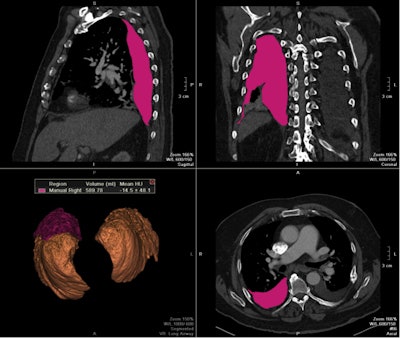

| Images show three traditional multiplanar reformatted reconstructions (MPRs) and one 3D reconstruction of final segmented pleural effusion volumes using a semiautomated quantification method (above) and manual method (below) on the same patient. The semiautomated segmentation method calculated a pleural effusion volume of 571.97 mL, a difference of less than 3% compared with 589.79 mL on manual segmentation. All images courtesy of Dr. Marcos Botelho. |